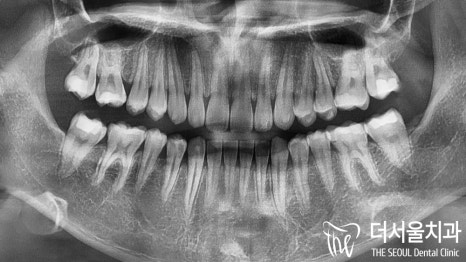

어금니 뒤쪽은 배열에서 벗어나

삐뚤어져 있는 총생을 갖고 있었습니다.

이를 크라우딩(crowding)이라 부릅니다.

맨 뒤에있는 어금니가 올바른 맞물림이 아니라

바깥 쪽으로 뻐드러져 교합이 되지 않고 있었는데요.

다행히 골격적인 문제는 없었으나

심한 딥바이트로 인해 저작이나 절단 등

치아 기능이 제대로 되지 않고 있었습니다.

본원에서는 윗니와 아랫니의 함입으로

교합관계를 긴밀하게 바꿔주면서

과개교합(Deep bite)를 개선시키기로 했습니다.